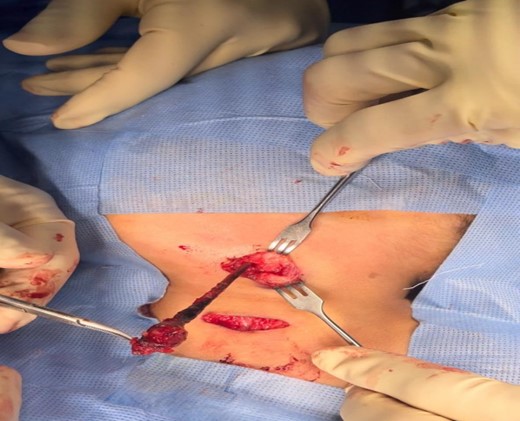

After draping and sterilisation, the small left-sided neck punctum was identified, probing of the fistula tract by a lacrimal probe was done, followed by the insertion of an arterial catheter inside the fistula tract (Fig. 6). The amount of methylene blue added was 0.01 ml per 2 ml of fibrin glue, and a total of 4 ml of this mixture was injected. This mixture allows the glue to be dyed adequately and does not inhibit its solidification. The arterial catheter was totally inserted, about 7 cm in length, and injection of methylene blue with fibrin glue was performed using an arterial catheter inside the tract. An elliptical incision was made around the fistula opening, followed by dissection of the tract. The tract was obvious, firm and colored with methylene blue. The tract was easily dissected without the need to remove extra tissues around it. Another superior incision, a step ladder incision, was made as the tract was long. The tract followed to its entry into the tonsillar fossa, which was ligated. The internal carotid artery, internal jugular vein, hypoglossal nerve and glossopharyngeal nerve were all identified and preserved. Bilateral tonsillectomy was performed, and the tract was visualised within the left tonsil (Figs 1–4). The left tract at the tonsillar bed after the tonsillectomy was ligated and cauterised. Then bilateral auricular sinus excision is done. The patient was then seen after 3 months of surgery and was doing well.

The branchial firm colored tract seen clearly after delivery it by upper step ladder incision. Notice the tract removed without excessive tissue removal around it.